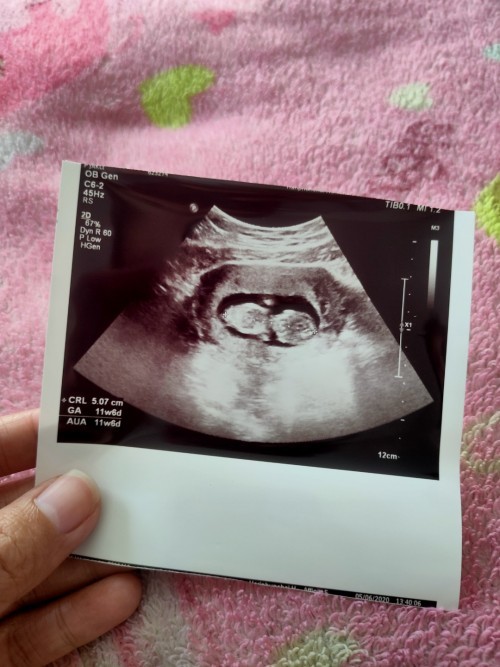

เราฝาดท้องครั้งแรกที่ 11week ก็เจอน้องตัวขนาดนี้แล้วนะคะแม่

บ้านนี้ซาวด์ตอน8วีคก้อเจอตัวน้องพร้อมเสียงหัวใจเลยค่ะ